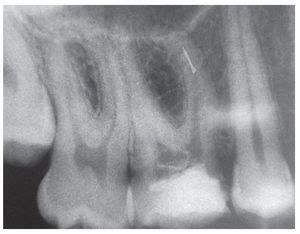

Diente 16 con instrumento de NiTi fracturado en el conducto mesiovestibular

Diente 16 una vez retirado el fragmento

Utilizando instrumentos manuales de acero inoxidable precurvados fue posible establecer una vía de instrumentación